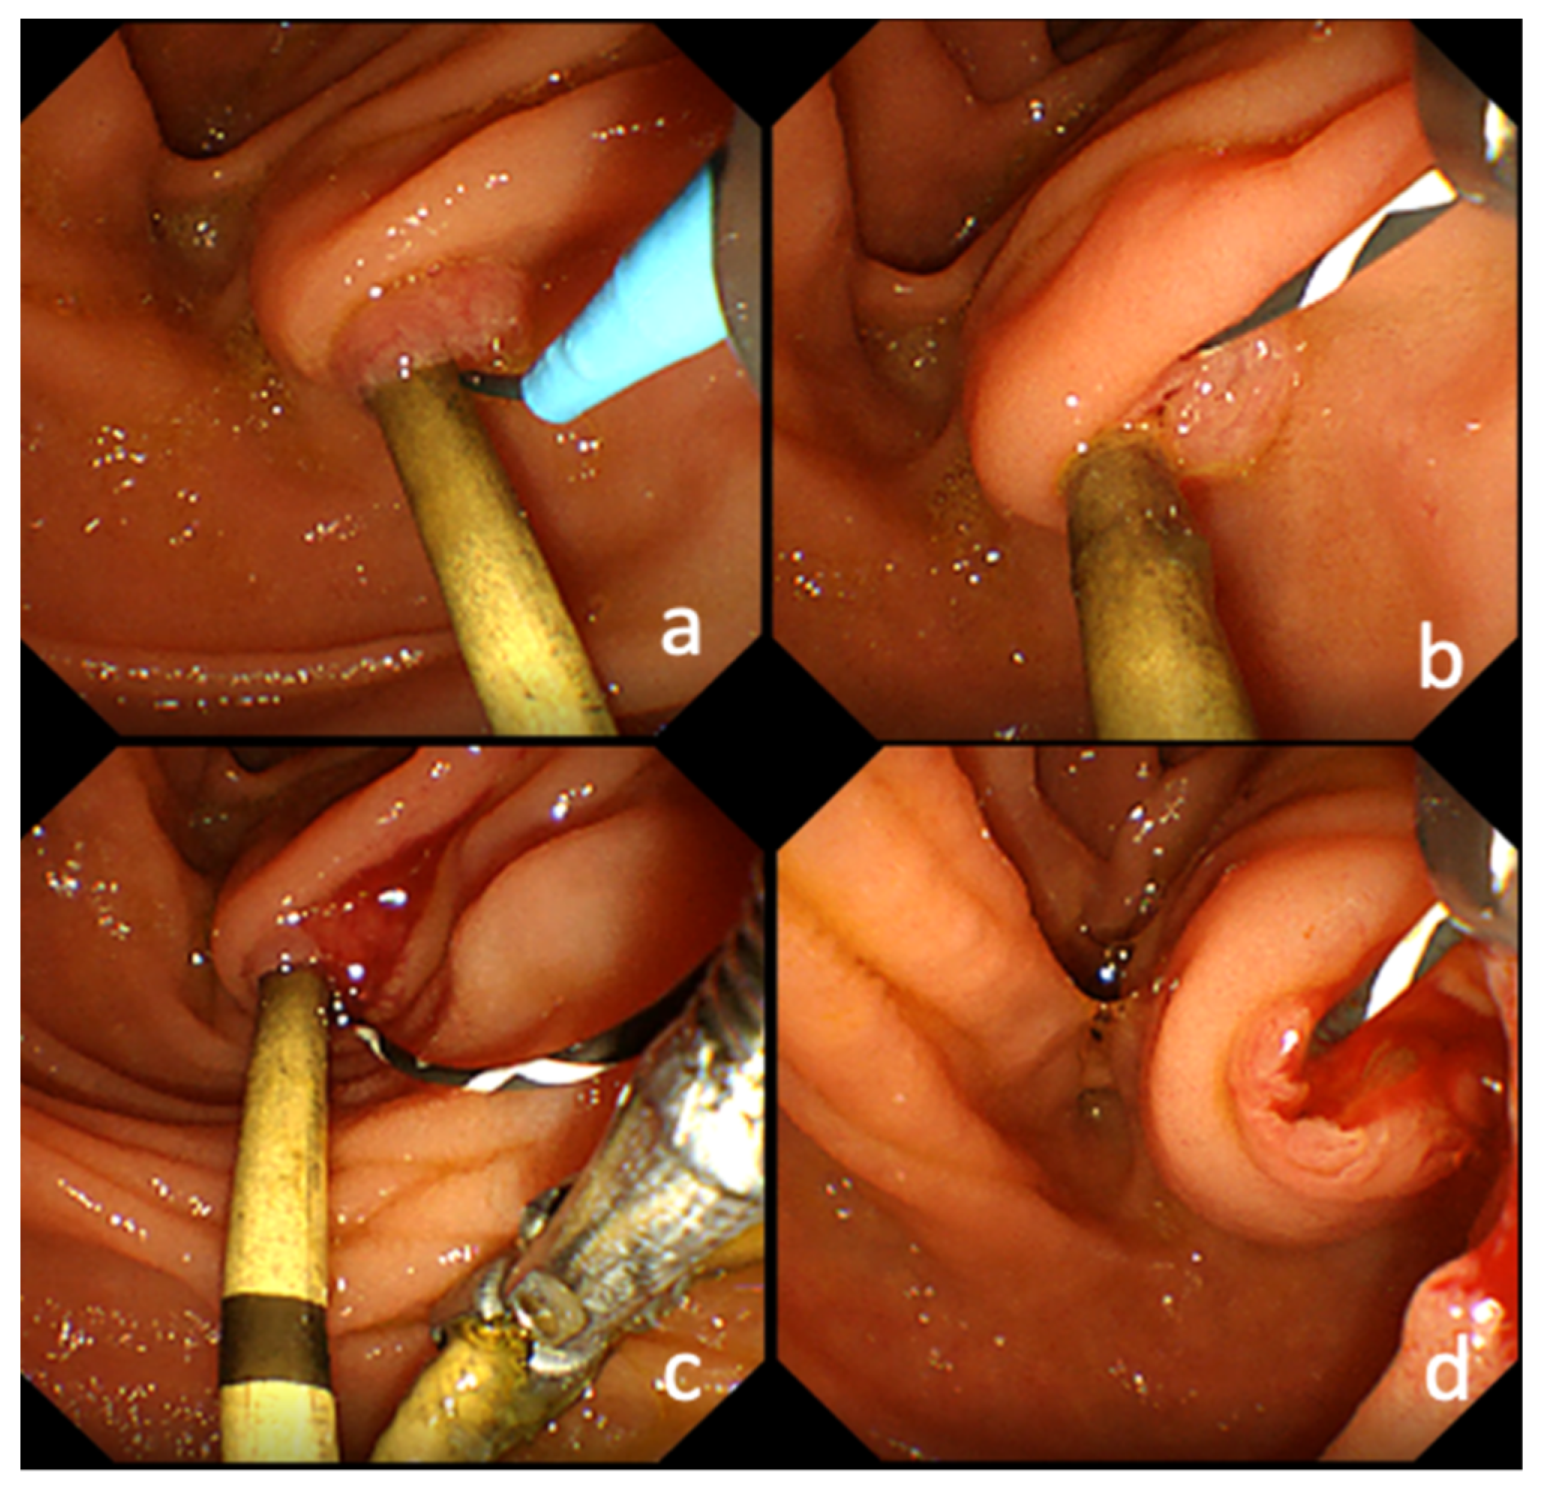

2.4. Endoscopic Replacement of Transpapillary Biliary PS

4.2. PS Removal While Leaving the GW